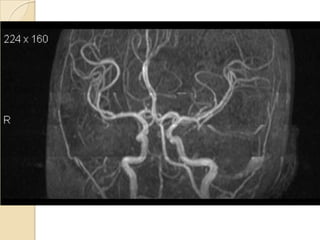

NORMAL MRA

Arteries of the brain (cranial view) - MRA

1. Anterior cerebral artery

2. Anterior communicating artery

3. Basilar artery

4. branches (in insula) of middle

cerebral artery

5. Cavernous portion of internal

carotid artery

6. Cervical portion of internal carotid

artery

7. Genu of middle cerebral artery

8. Intracranial (supraclinoid) internal

9. Middle cerebral artery

10. Ophthalmic artery

11. Petrous portion of internal carotid

12. Posterior cerebral artery

13. Posterior cerebral artery in ambient

cistern

14. posterior cerebral artery in

interpeduncular cistern

15. Posterior communicating artery

16. Posterior inf cerebellar artery.

17. Quadrigeminal portion of posterior

18. Superior cerebellar artery

19. Vertebral artery

Arteries of the brain (lateral view) - MRA